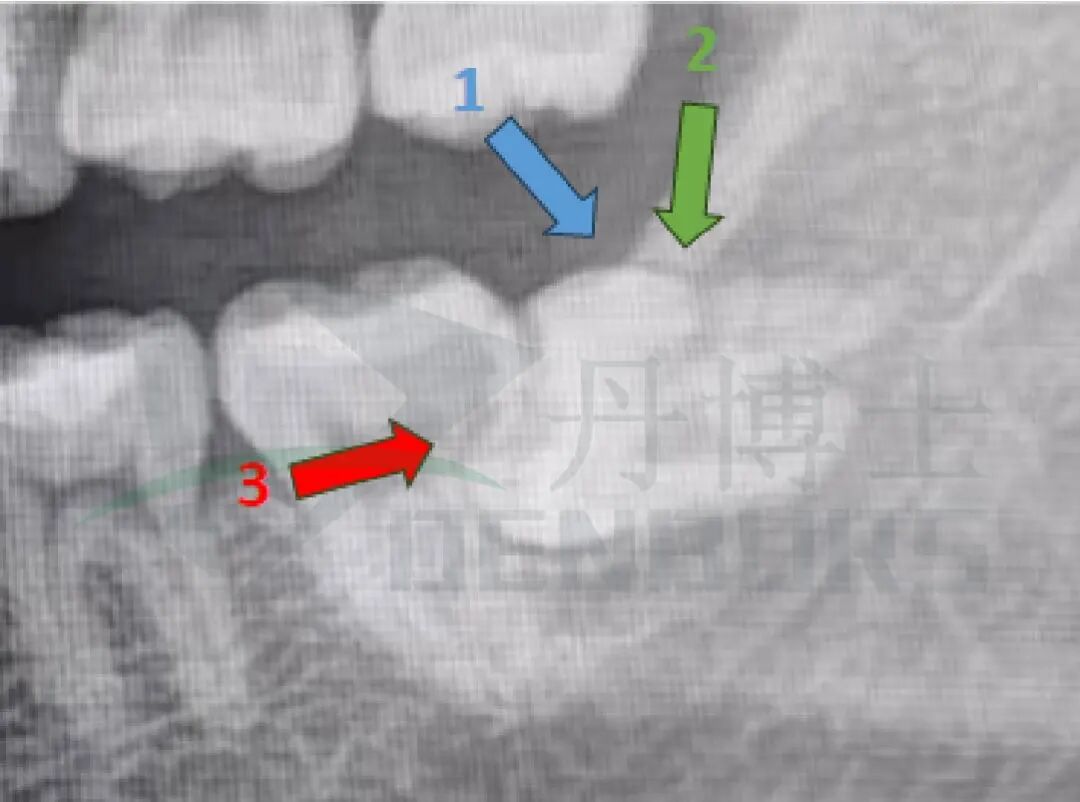

影像学检查

全景片显示:38近中水平高位阻生,37远中邻面部分透射影。

阻力分析

• 龈瓣覆盖: 牙龈阻力

• 远中骨覆盖:骨阻力

• 近中部分阻碍邻牙:牙冠阻力

• 临近的解剖结构:37邻牙,下牙槽神经管